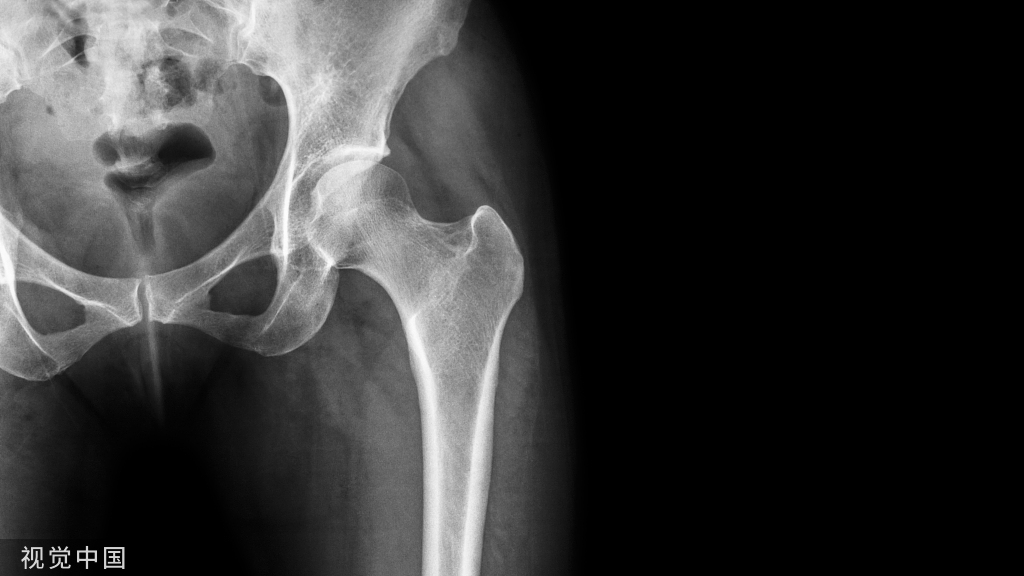

影像学诊断

在足正位X线上,第1、2、3跖骨的内外侧缘分别和它相对应的楔骨的内外侧缘呈一直线排列;第一、二跖骨基底间隙和内中楔骨间隙相等。

30°斜位上:1、第四跖骨内侧缘和骰骨内侧缘连续成一条直线2、第三跖骨内侧缘和外侧楔骨内侧缘连续成一条直线3、第二、三跖骨基底间隙和内、中楔骨间隙相等。

侧位上,跖骨不超过相应楔骨背侧缘。从远端的跖骨经过跖跗关节到近端的跗骨,应该是一条不间断的连线

2005年Pearse等提出“ABC”的方法来阅读足部X 线片, 以减少中、前足的漏诊。 A ( alignment)检查跖骨与相应楔骨的对应线 B ( bone)检查每一块骨的轮廓 C ( congruity )检查整体一致吻合, 在正位片上观察内柱, 在斜位片上观察中、外柱。侧位片的常规检查可发现Lisfranc关节矢状面的半脱位及撕脱性骨折

特殊放射学检查应力位摄片:评价跖跗关节的稳定性负重位摄片:评价足的纵弓的稳定性,以及明确第1跖骨间隙的增宽 外侧斜位:诊断细微的第1跖骨间隙的增宽CT 扫描:诊断不明显的跖跗关节半脱位对照位摄片:明确细微的损伤